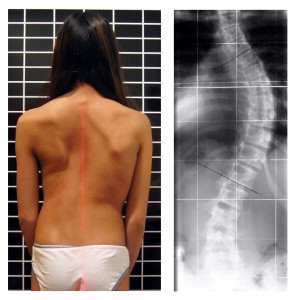

Lo staff del Centro San Marco è composto da specialisti nella rieducazione funzionale di ginocchio, anca, spalla, scoliosi, mal di schiena, patologie croniche ma anche semplicemente per stare in forma.